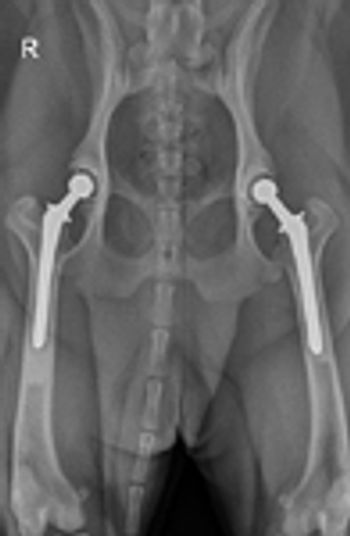

Metallic implants placed in the body should be corrosion-resistant, biocompatible, and must have adequate strength to withstand functional stress. Corrosion of metal occurs because of the electrochemical ions in body fluid. Most metal implants currently used in veterinary surgery are of 316L stainless steel.